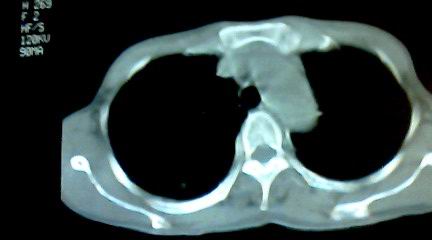

标题: CT25218:请教!胸部CT,胸8椎体骨质破坏,伴周围软组织肿。 [打印本页]

标题: CT25218:请教!胸部CT,胸8椎体骨质破坏,伴周围软组织肿。

患者,女41岁,肢体乏力。

两肺上叶继发性肺结核;胸椎结核并椎旁寒性脓肿形成。

胸椎结核并椎旁寒性脓肿形成。